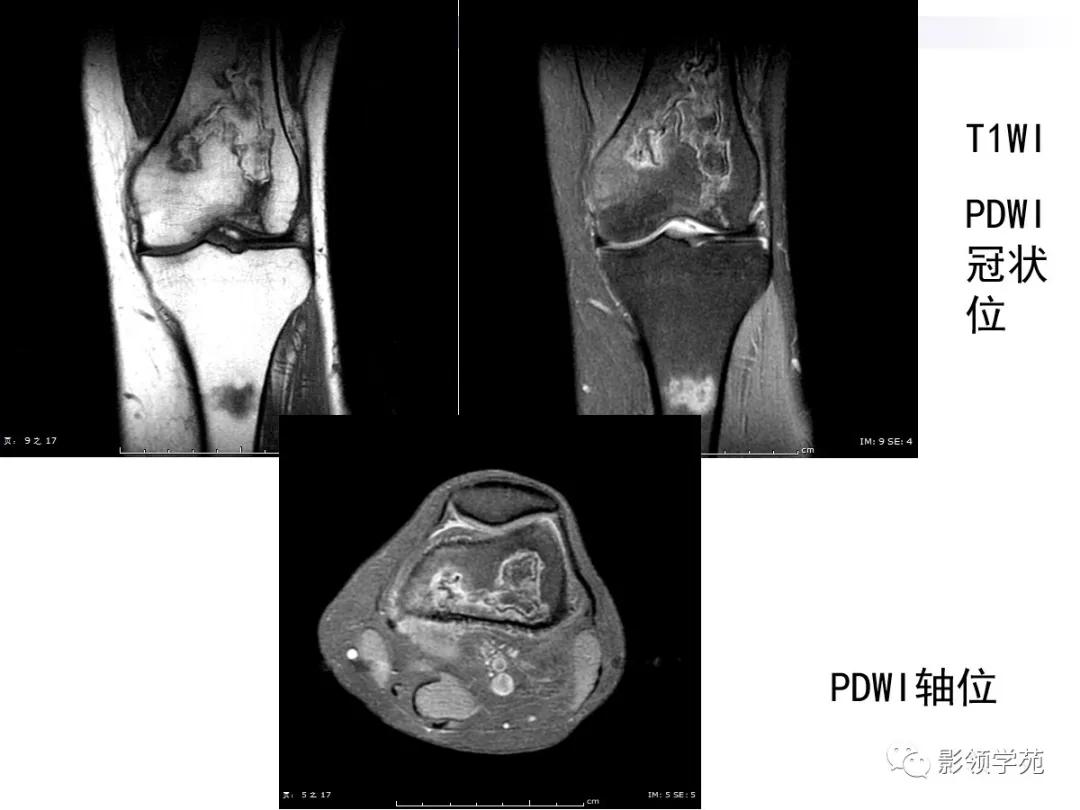

病例2:女性,45岁,病史:临床诊断SLE10年,膝关节疼痛4年。

MRI:呈不规则片状、斑片状混杂信号,病灶中央T1WI呈等、低信号,T2WI等、高信号,内部信号不均匀。

MR:T1及T2均呈不规则的混杂片状低信号影,周围可见线状低信号单环征

患者因临床反复发作,新旧病灶同时存在,所以骨梗死以多发性、多形性、多期表现并存。